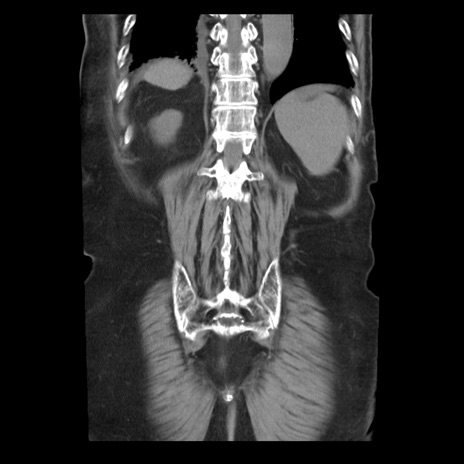

横断像